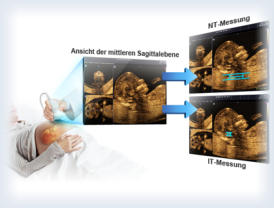

Ultraschalluntersuchungen

3D/4D-Ultraschall

Fundierte

Fachkenntnis

kombinieren

wir

mit

modernster

Medizintechnik.

Für

Untersuchungen

setzen

wir

den

premium

3D/4D Farbdoppler Accuvix A30 von Samsung ein.